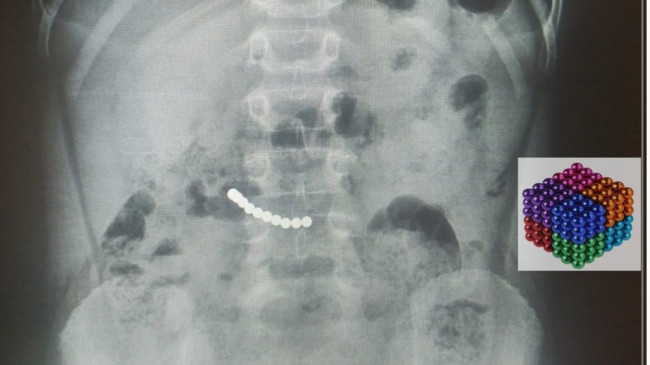

Karın ağrısı şikayetiyle Muğla Eğitim ve Araştırma Hastanesi’ne başvuran 7 yaşındaki U.K.’nin kontrollerinde, midesinde mıknatıs olduğu belirlendi.

Yaklaşık iki saat süren operasyonla çocuğun midesindeki 11 mıknatıs çıkarıldı.